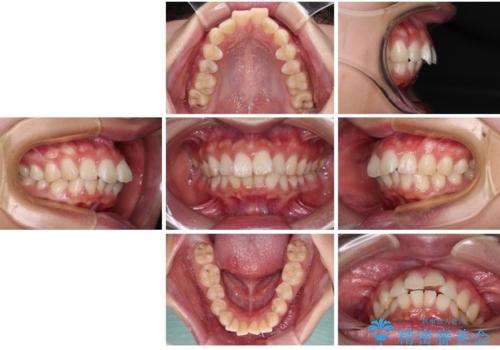

口元が出ているのを改善したい。 クリアブラケットによる抜歯矯正

- 20代女性

- 1年10ヶ月

- 前歯部のデコボコと口元が出ているのが気になるとのことで来院された患者様です。

口元の突出感の解消と、このままデコボコを解消するとさらに出っ歯傾向になってしまうことを考慮し、上下左右の小臼歯を抜歯しクリアブラケットにて矯正していくこととしました。

舌突出癖を改善するトレーニングを一生懸命やっていただいたおかげで2年以内に治療を終えることができました。